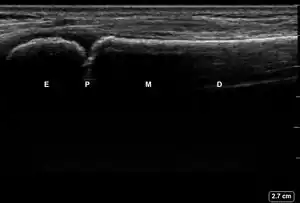

![]() Ultrasound lateral view of normal radius. E = epiphysis; P = physis; M = metaphysis; D = diaphysis. | |